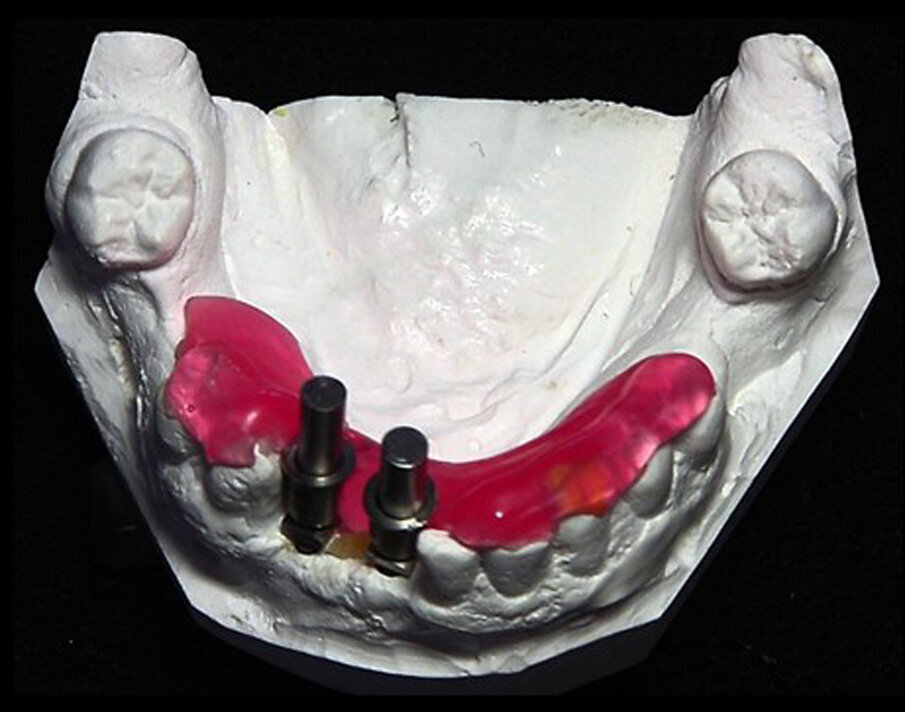

Figs. 3a & b: Guide sleeves were placed over the guide posts with the retentive cleats at the lingual aspect

At two weeks post-extraction and socket grafting, the patient presented and sutures were removed. The flap had healed uneventfully with primary closure. The patient was scheduled for an appointment at three months post-grafting to initiate the next phase of treatment. An impression was taken of the arch to fabricate the diagnostic guide. The impression was poured in stone to create a cast. A 3/32 in. drill was used in a laboratory handpiece to create a pilot hole in the cast at the estimated position and angulation at the central incisor and canine sites on the edentulous area, and guide posts (DePlaque) were inserted into the holes (Fig. 2). Owing to the different anatomical shapes of the two sites, the pilot holes were placed based on the cast’s anatomy and parallelism was not attempted. A guide sleeve (DePlaque) was placed over each of the two guide posts and the retentive cleats were positioned at the lingual aspect (Figs. 3a & b). Triad gel (Dentsply Sirona) was placed over the retentive cleats on the sleeves and over the lubricated surfaces of the adjacent teeth on the cast and lightpolymerised to create the diagnostic guide (Figs. 4a & b). A CBCT scan was taken with the diagnostic guide worn intra-orally. The data was imported into CS 3D implant planning software (Carestream Dental), and the position of the two sleeves were analysed with regard to orientation to the underlying ridge and its angulation.